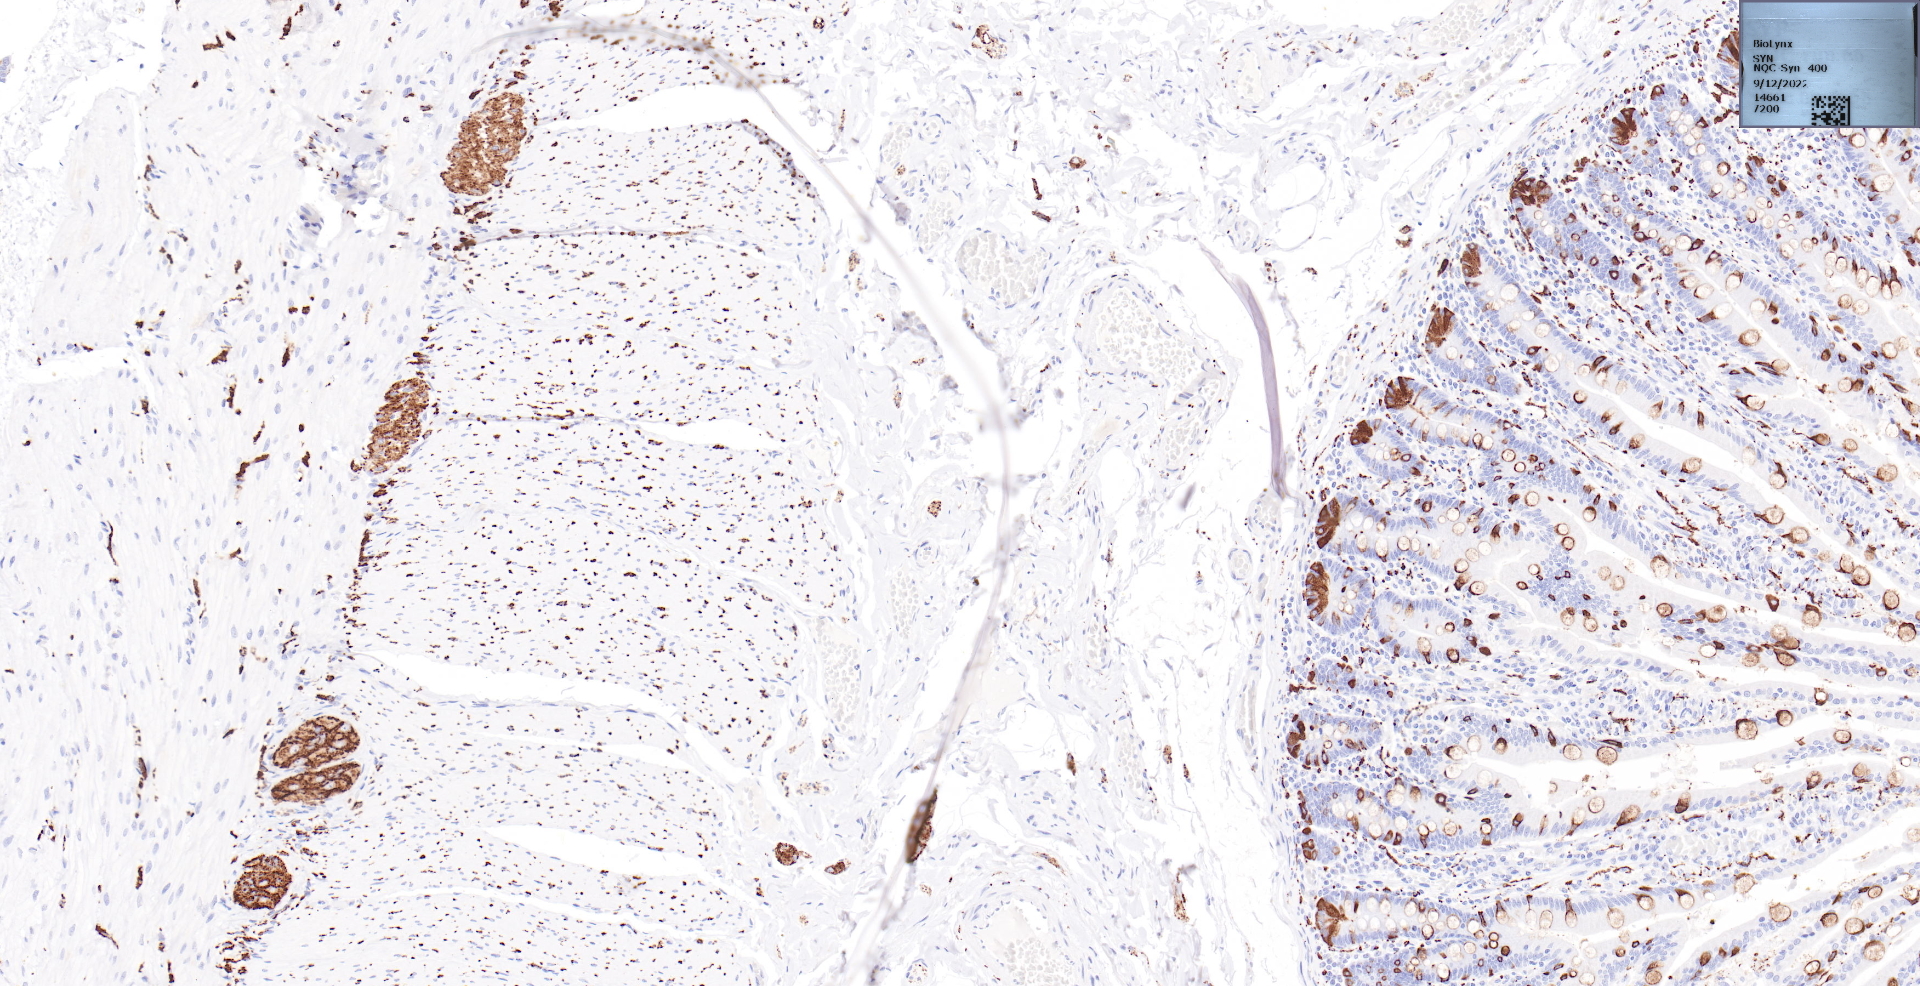

SYP(Synaptophysin)

十二指肠.jpg

BP6053 Synaptophysin十二指肠染色